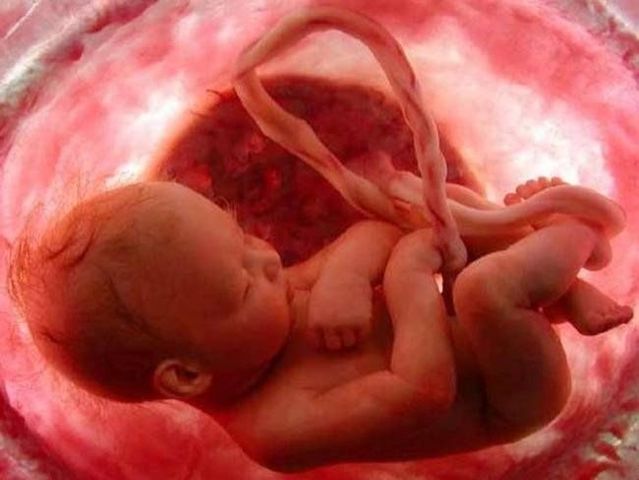

Aparecen las manos con todos sus dedos, las piernas se alargan, aparecen los pies con todos sus dedos, primero las muñecas y después los tobillos,la cabeza ya no está tan desproporcionada y el cuerpo empieza a alargarse, la cara va tomando una forma más normal: los ojos migran a la parte frontal, se forman los párpados y la boca ya puede incluso abrirse,los huesos siguen su crecimiento, la cola embrionaria del final de la columna vertebral desaparece,se forma el tubérculo genital

Se empiezan a formar la lengua, el paladar y los primordios de los dientes, aparecen primero los codos y después las rodillas, los dedos de las manos y los pies se separan y aparecen las uñas, las manitas se abren y cierran constantemente, aparece el lanugo,se forma el ano y el surco uretral, se inicia la osificación del esqueleto, los huesos acumulan calcio,los órganos sexuales empiezan a diferenciarse, el saco vitelino se va encogiendo porque la placenta está en pleno funcionamiento.

La sangre ha empezado a circular por el cordón umbilical, entre el feto y las membranas unidas a la pared uterina. El feto comienza a depender de esas membranas para alimentarse y la placenta inicia su funcionamiento.

La placenta ya ha adquirido su forma definitiva, seguirá creciendo y engrosando aunque ya está delimitada. Ésta se encarga de la producción de diversas hormonas, entre ellas los estrógenos y la progesterona.